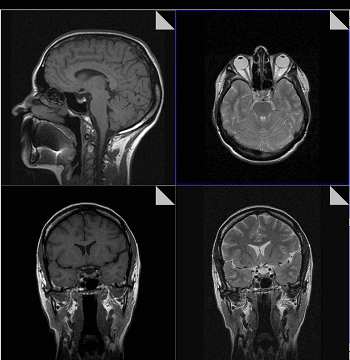

Что показывает МРТ

Магнитно-резонансная томография или МРТ - это сфокусированный метод, который проводит очень детальное обследование. Диагностическая точность МРТ превышает УЗИ и во многих случаях КТ, за исключением сканирования полых органов (легких, желудка, кишечника) и костей. МРТ является золотым стандартом диагностики:

- заболеваний головного и спинного мозга;

Принцип работы МРТ основан на эффекте ядерного магнитного резонанса. МР томограф в своей конструкции имеет мощный магнит, который создает магнитное поле, и датчик, который подает радиочастотные сигналы. В такой ситуации протоны атомов водорода начинают колебательные движения, выделяя при этом импульсы. Их улавливает компьютер томографа и преобразовывает в трехмерные изображения. Чем больше воды содержится в клетках ткани, тем детальней получается ее изображение. Поэтому на МРТ хорошо отображаются органы с большим содержанием воды: МРТ головного мозга, МРТ спинного мозга, МРТ глазных орбит, МРТ органов малого таза, МРТ позвоночника, МРТ суставов, и плохо визуализируются органы с большим содержанием воздуха МРТ органов грудной клетки или кости.

В основе МРТ лежит явление магнитного резонанса, основанного на переизлучении радиоволн, взаимодействующих с атомами водорода, в избытке содержащимися в организме человека. Эти переизлученные электромагнитные волны улавливаются датчиком МР-томографа, усиливаются и в виде цифровых изображений появляются на экране монитора. Это безвредный и абсолютно безопасный для здоровья человека метод лучевой диагностики, так как в основе получения изображения отсутствует рентгеновское излучение, поэтому МРТ можно проходить неограниченное количество раз, с любым интервалом.

Существенное преимущество МР-томографии перед КТ заключается в том, что она не противопоказана беременным во II и III триместре и совершенно безопасна для детей. В МРТ исследуемая область сканируется в трех проекциях, что позволяет врачу-рентгенологу в полной мере оценить состояние тканей и органов исследуемой области, а высокая контрастность изображения и пространственное разрешение позволяют визуализировать серое и белое вещество головного мозга, оценивать состояние костного мозга и мягких тканей различной локализации. Кроме того, метод МРТ позволяет получать изображения сосудов головного мозга и сосудов шеи без введения контрастного препарата.

Мы также всегда делаем КТ пациентам с подозрением на нарушение мозгового кровообращения, исследование позволяет не только подтвердить диагноз, но и оценить «масштаб» поражения и выработать верную тактику. Назначают его при патологии почек, в частности, при наличии камней. На томографе можно увидеть их расположение, оценить плотность и структуру, а значит, принять решение об операции или выборе консервативных методов. МРТ имеет преимущества при изучении патологий суставов, для диагностики заболеваний головного мозга, спинного мозга, органов малого таза.

Есть некоторые органы, обследование которых рекомендуют начинать с проведения МРТ. В частности, речь идет о головного мозге. С помощью УЗИ оценить его строение у взрослых очень проблематично, т. к. со всех сторон мозг заключен в череп, который практически не пропускает ультразвуковых волн. Для МРТ это не является препятствием.